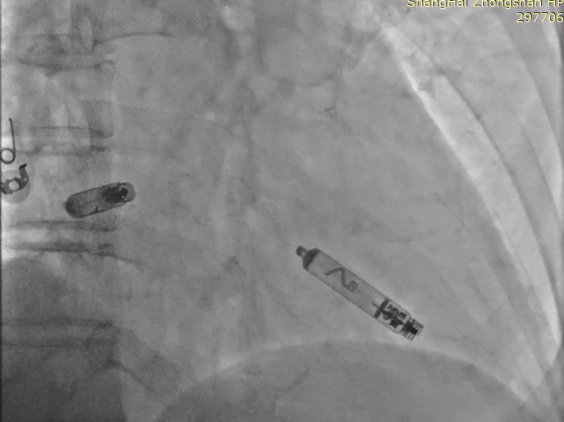

以上两位患者均以标准流程成功植入Aveir™ DR,最终固定位置影像:

病例1 RAO

病例1 LAO

病例2 RAO